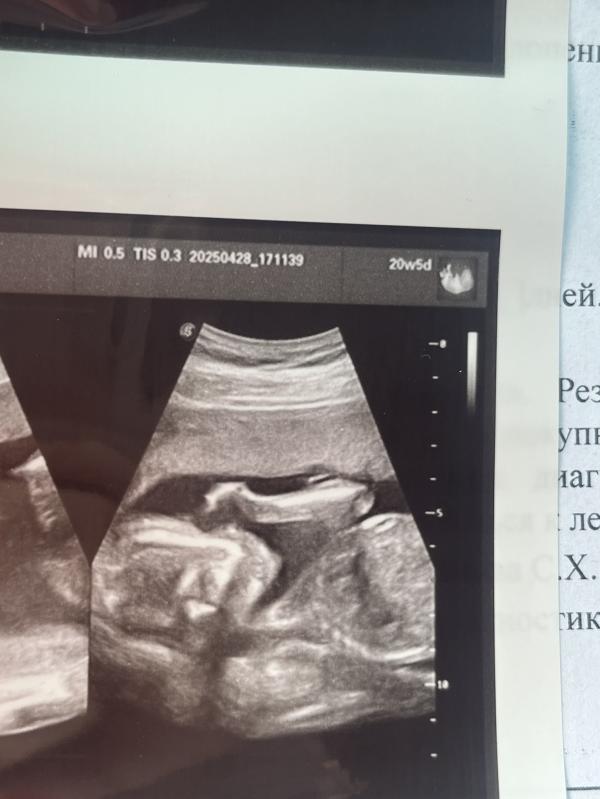

Узнали пол. Моя родная, любимая ДОЧЬ.💖

Всё УЗИ дралась, махала ручкой. Всё сразу показала, не стеснялась.😂